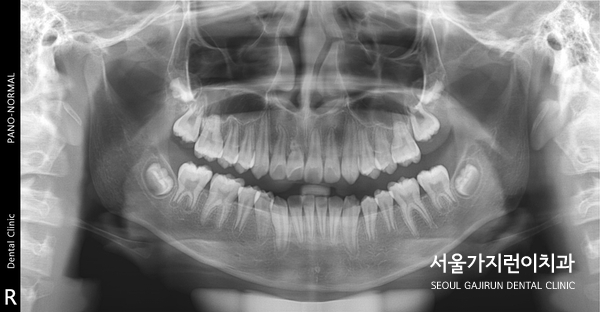

해당 환자분의 경우 8세의 남아였는데요. 앞니가 180도로 돌아간 상태로 매복된 것을 확인할 수 있었습니다. 거꾸로 숨어있던 건데요. 매복된 치아의 견인을 위해 치아에 버튼을 달고 치근 흡수를 조심하면서 아주 약한 힘으로 견인치료를 진행했습니다.

다행히 치료를 시작한 지 14개월 만에 앞니가 형태를 보이고 자리를 잡아갔는데요. 이 케이스의 경우 비교적 일찍 치아교정을 시작했다는 전제조건이 있었는데요. 매복된 치아가 잇몸뼈와 심하게 유착이 되었다면 교정력을 아무리 주어도 치아가 내려오지 않을 가능성이 있었습니다. 그렇기 때문에 상악 중절치의 매복을 비롯한 치아 맹출 장애는 치아교정전문치과에서 진료를 받아야 하는데요.

이 외에도 더 다양한 사례들은 블로그에 기록해두었는데요. 성장기 자녀가 있다면 정기적으로 치과 검진을 받고 방사선 사진으로 치아의 맹출 및 발육 상태를 확인해 올바른 치아 발육을 위해 체크해보는 게 좋겠습니다.